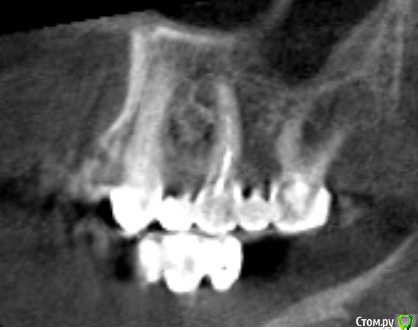

Мк стоят около 10 лет,в области 23 средней 1/3 определяется свищ,отделяемого нет,небольшое западение альвеолярного отростка с рубцовыми изменениями слизистой в области 24 ,перкуссия 23,25 безболезненна,болезненность в области переходной складки и небной поверхности на уровне апекса 23

Со слов пациента периодически возникающий отек,тянущие боли

Около недели назад был похожий случай: пациент мост 1.6-1.4. В промежутке неясного генеза убыль кости по снимку. Делаем КТ - очаг просветления в области отсутсвующего зуба, по снимку  вроде кость 4 типа. Объясняю пациенту, что будем ставить имплантат, раскроемся и увидим что там. День Х, после отслоения в области удаленного зуба 1.5 грануляционная ткань! 30 минут кюретажа всех этих спаек и получена практически первоначальная лунка удаленного зуба 1.5. Закинул кость и вкрутил имплантат. Ушил, а на момент когда пациент вышел из кресла - сказал, что сало прям легче. мол было даже желание вам доктор помочь все это из лунки убрать))) 2 недели все гуд - ничего не беспокоит. Так вот к чему так много букав: скорее всего удалили зуб и не сделали кюретаж, там грануляционная ткань которая дает всю эту картину. Побольше бы срезов с КТ. И сделайте сагитальные срезы. Если полость из неоткуда то режьте и смотрите.